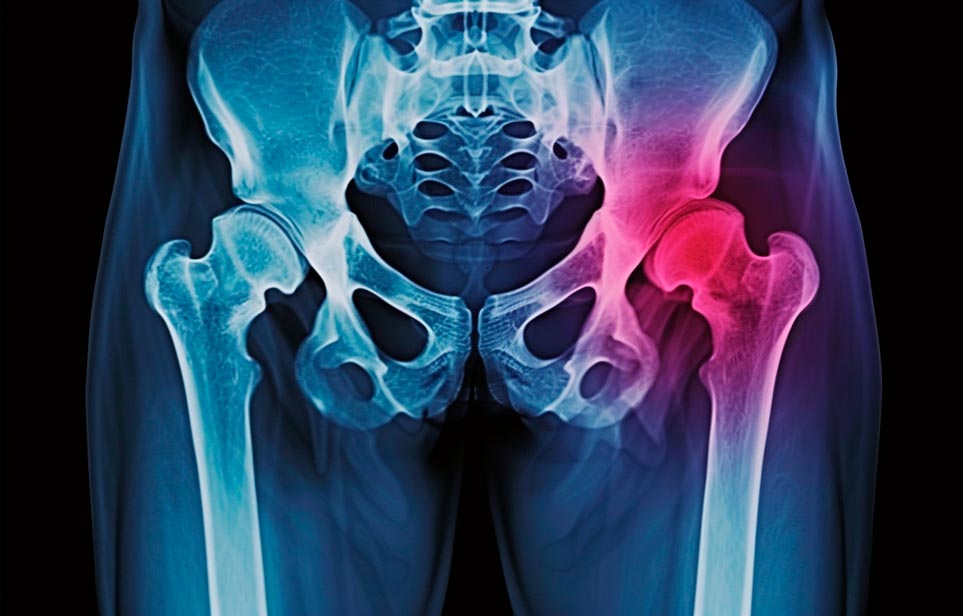

Реабилитация пожилых после перелома шейки бедра в Новосибирске

Эффективная и профессиональная реабилитация после перелома шейки бедра в Новосибирске осуществляется по демократичным ценам лучшими специалистами современной медицинской клиники «Заботливые люди» с применением персонального подхода к каждому пожилому человеку с такой тяжёлой травмой бедренной кости ноги. В процессе осуществления такой специализированной услуги все наши пациенты имеют возможность получения качественного и достойного обслуживания, эффективного восстановления. Лучший дом престарелых позаботиться о Вашем близком человеке.

Такая травма в большей части случаев возникает у граждан преклонного возраста. При её появлении на протяжении длительного времени сохраняются болевые и неприятные ощущения в области паха, при которых серьёзно ухудшается качество жизни, возникает множество последствий для его жизни и здоровья.

По какой симптоматике можно определить перелом шейки бедра

Выявить его можно по возникновению следующей тревожной симптоматики:

- Визуально повреждённая нога сокращается на несколько сантиметром из-за сокращения мышц.

- Стопа выворачивается наружу.

- В лежачем положении человек не может поднять ногу.

При такой симптоматике важно незамедлительно обращаться к специалистам для получения всей необходимой помощи, терапии и восстановления после перелома шейки бедра. Если не оказать помощи старику, то это приведёт к гноению, инвалидности, иным видам осложнений.